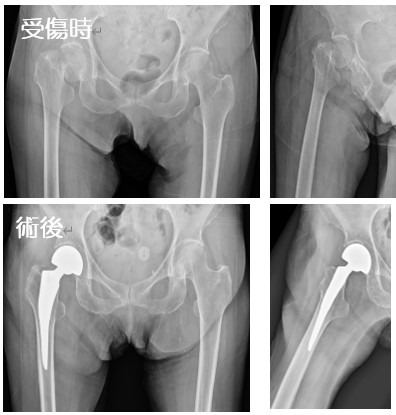

2020-07-21 手外科・外傷 ページ内リンク 髄内釘(short femoral nail) Sliding hip screw 大腿骨頚部骨折(骨接合術) 大腿骨頚部骨折(人工骨頭挿入術) 腿骨転子部骨折(髄内釘) 髄内釘(short femoral nail) Sliding hip screw 大腿骨頚部骨折(骨接合術) 大腿骨頚部骨折(人工骨頭挿入術) 腿骨転子部骨折(髄内釘) 露口 和陽 外傷・手外科部長 整形外科手外科・外傷 詳しく見る 関 謙太朗 整形外科肩関節外科手外科・外傷 詳しく見る 関連ページ 手外科・外傷 一覧へ戻る